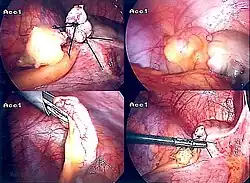

Laparoscopic appendectomy

Laparoscopic appendectomy was introduced in 1983 and has become an increasingly prevalent intervention for acute appendicitis.[95] This surgical procedure consists of making three to four incisions in the abdomen, each 0.25 to 0.5 inches (6.4 to 12.7 mm) long. This type of appendectomy is made by inserting a special surgical tool called a laparoscope into one of the incisions. The laparoscope is connected to a monitor outside the person's body, and it is designed to help the surgeon inspect the infected area in the abdomen. The other two incisions are made for the specific removal of the appendix by using surgical instruments. Laparoscopic surgery requires general anesthesia, and it can last up to two hours. Laparoscopic appendectomy has several advantages over open appendectomy, including a shorter post-operative recovery, less post-operative pain, and a lower superficial surgical site infection rate. However, the occurrence of an intra-abdominal abscess is almost three times more prevalent in laparoscopic appendectomy than open appendectomy.[96]